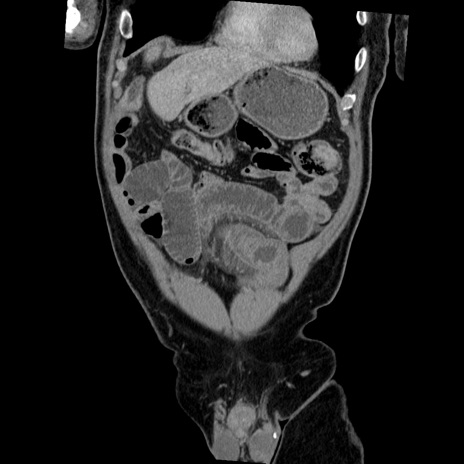

症例22(冠状断像)

【症例】50歳代男性

【主訴】腹痛

【現病歴】AVMからの被殻出血のため回復期リハ病棟入院中。 本日午後3時頃急に下腹部痛が出現した。

【既往歴】AVM、被殻出血、虫垂炎、高血圧

【身体所見】意識晴明、左半身不全麻痺、会話の理解は良好、36.5°C、腹部:膨隆、全体に板状硬、下腹部正中に圧痛点あり、反跳痛-、筋性防御不明、右下腹部にope scar

【データ】WBC 9400、CRP 0.06